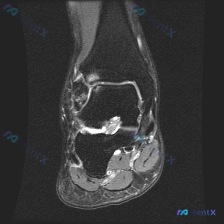

看到一个有意思的读片病例,问题是「这张影像存在什么发现,报告提示软骨异常」,整理了一下影像资料和分析思路,分享给大家。 病例基本影像信息 这是一张踝关节冠状位T2加权MRI,核心影像表现如下: 1. 距下关节间隙内可见明显异常高信号,提示关节积液或滑膜异常,高信号区域非常显著 2. 胫骨远端、距骨、...

看到一个有意思的踝关节病例,临床怀疑软骨异常,但单张MRI影像的表现和临床判断有矛盾,整理一下思路和大家分享。 一、现有病例与影像信息 本次提供的是踝关节MRI-T2序列轴位单张图像,已完成初步影像分析: 1. 影像基本表现: - 可见踝关节间隙及距下关节周围明显高信号积液影,提示关节腔内积液 -...